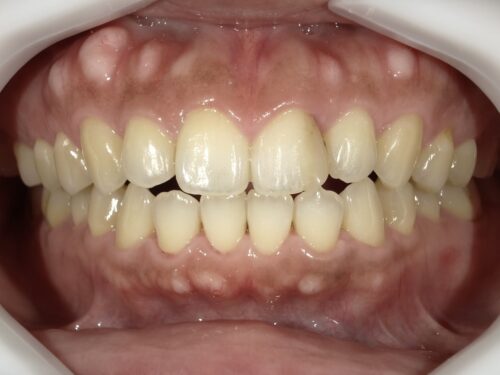

ホワイトニングからのCRで白い歯を手に入れる

①全体的に白くしたい

②前歯の古い詰め物を治したい

というお悩みで来院された患者さんです。

ただ、もう1箇所、この赤いマルで囲まれた部分をよーく見ていただくと、

ここに古い詰め物がついていて、変色しているのがわかります。

おそらく以前むし歯になって治療されたのだと思いますが、

コンポジットレジン(CR)という樹脂製の材料を使用されているようです。

この材料は、むし歯治療で使用されている材料なのですが、

時間経過とともにどうしても吸水して色が変わってしまうのです。